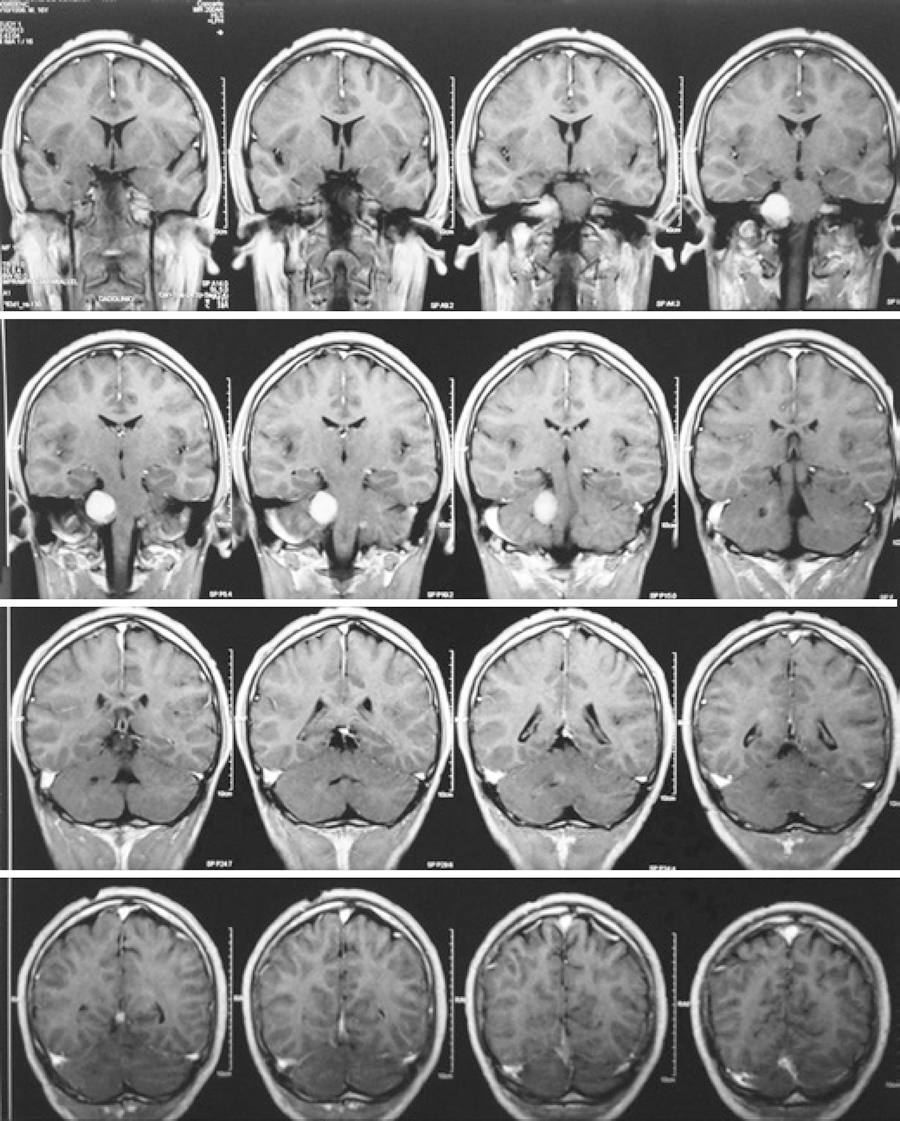

After surgical treatment of acquired restrictive strabismus, the child described remained stable with no other symptoms for approximately 7 years. By the age of 14 years, he developed left hand palsy and skin tumors. One year later, he started experiencing the beginnings of a hearing loss. Magnetic resonance imaging (MRI) of the brain revealed bilateral tumors indicative of vestibular schwannoma (Figure 1).

Figure 1 Magnetic resonance imaging with gadolinium demonstrating bilateral vestibular schwannomas with size predominance on the right side.

Subsequently, the patient was referred to the Neurofibromatosis Reference Center of the Universidade Federal de Minas Gerais for further evaluation. Diagnosis of neurofibromatosis type 2 (NF2) was then established according to MRI demonstrating bilateral vestibular schwannomas associated with cutaneous schwannomas.